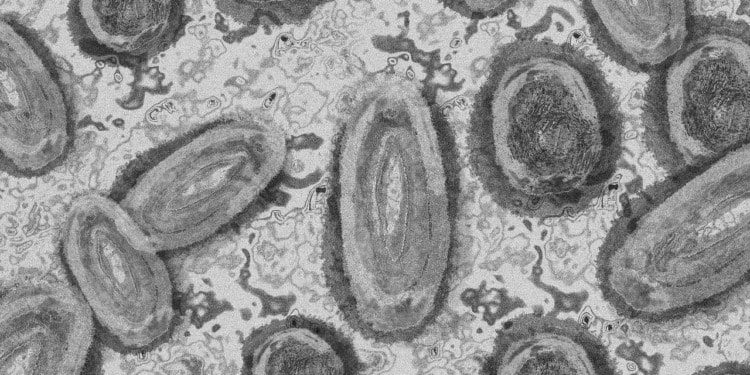

Editor’s Note: The opinions expressed here by Impakter.com columnists are their own, not those of Impakter.com — In the Featured Photo: Monkeypox virus. Featured Photo Credit: Pixabay.